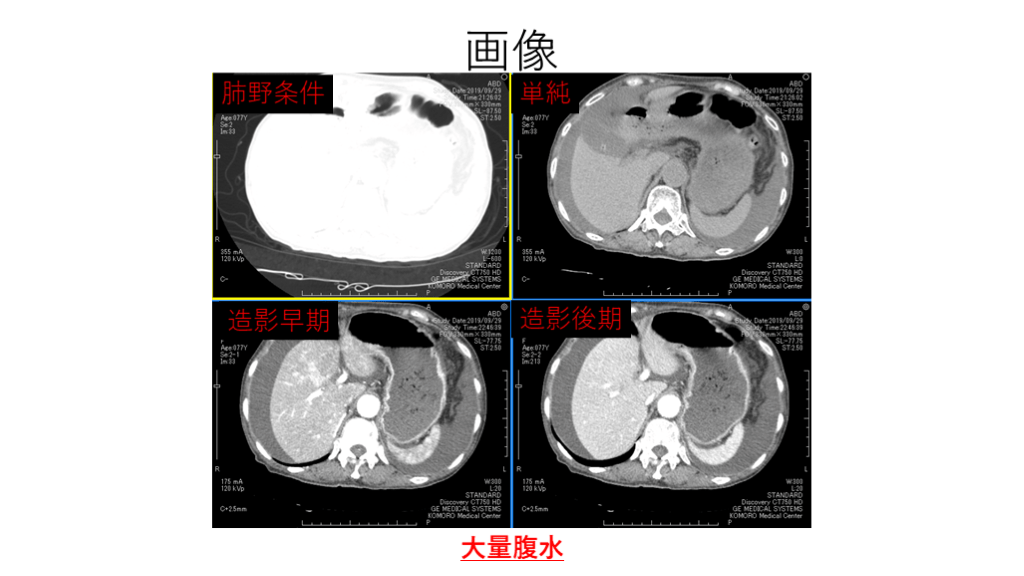

画像 大量腹水 肺野条件 造影後期 造影早期 単純

#7.